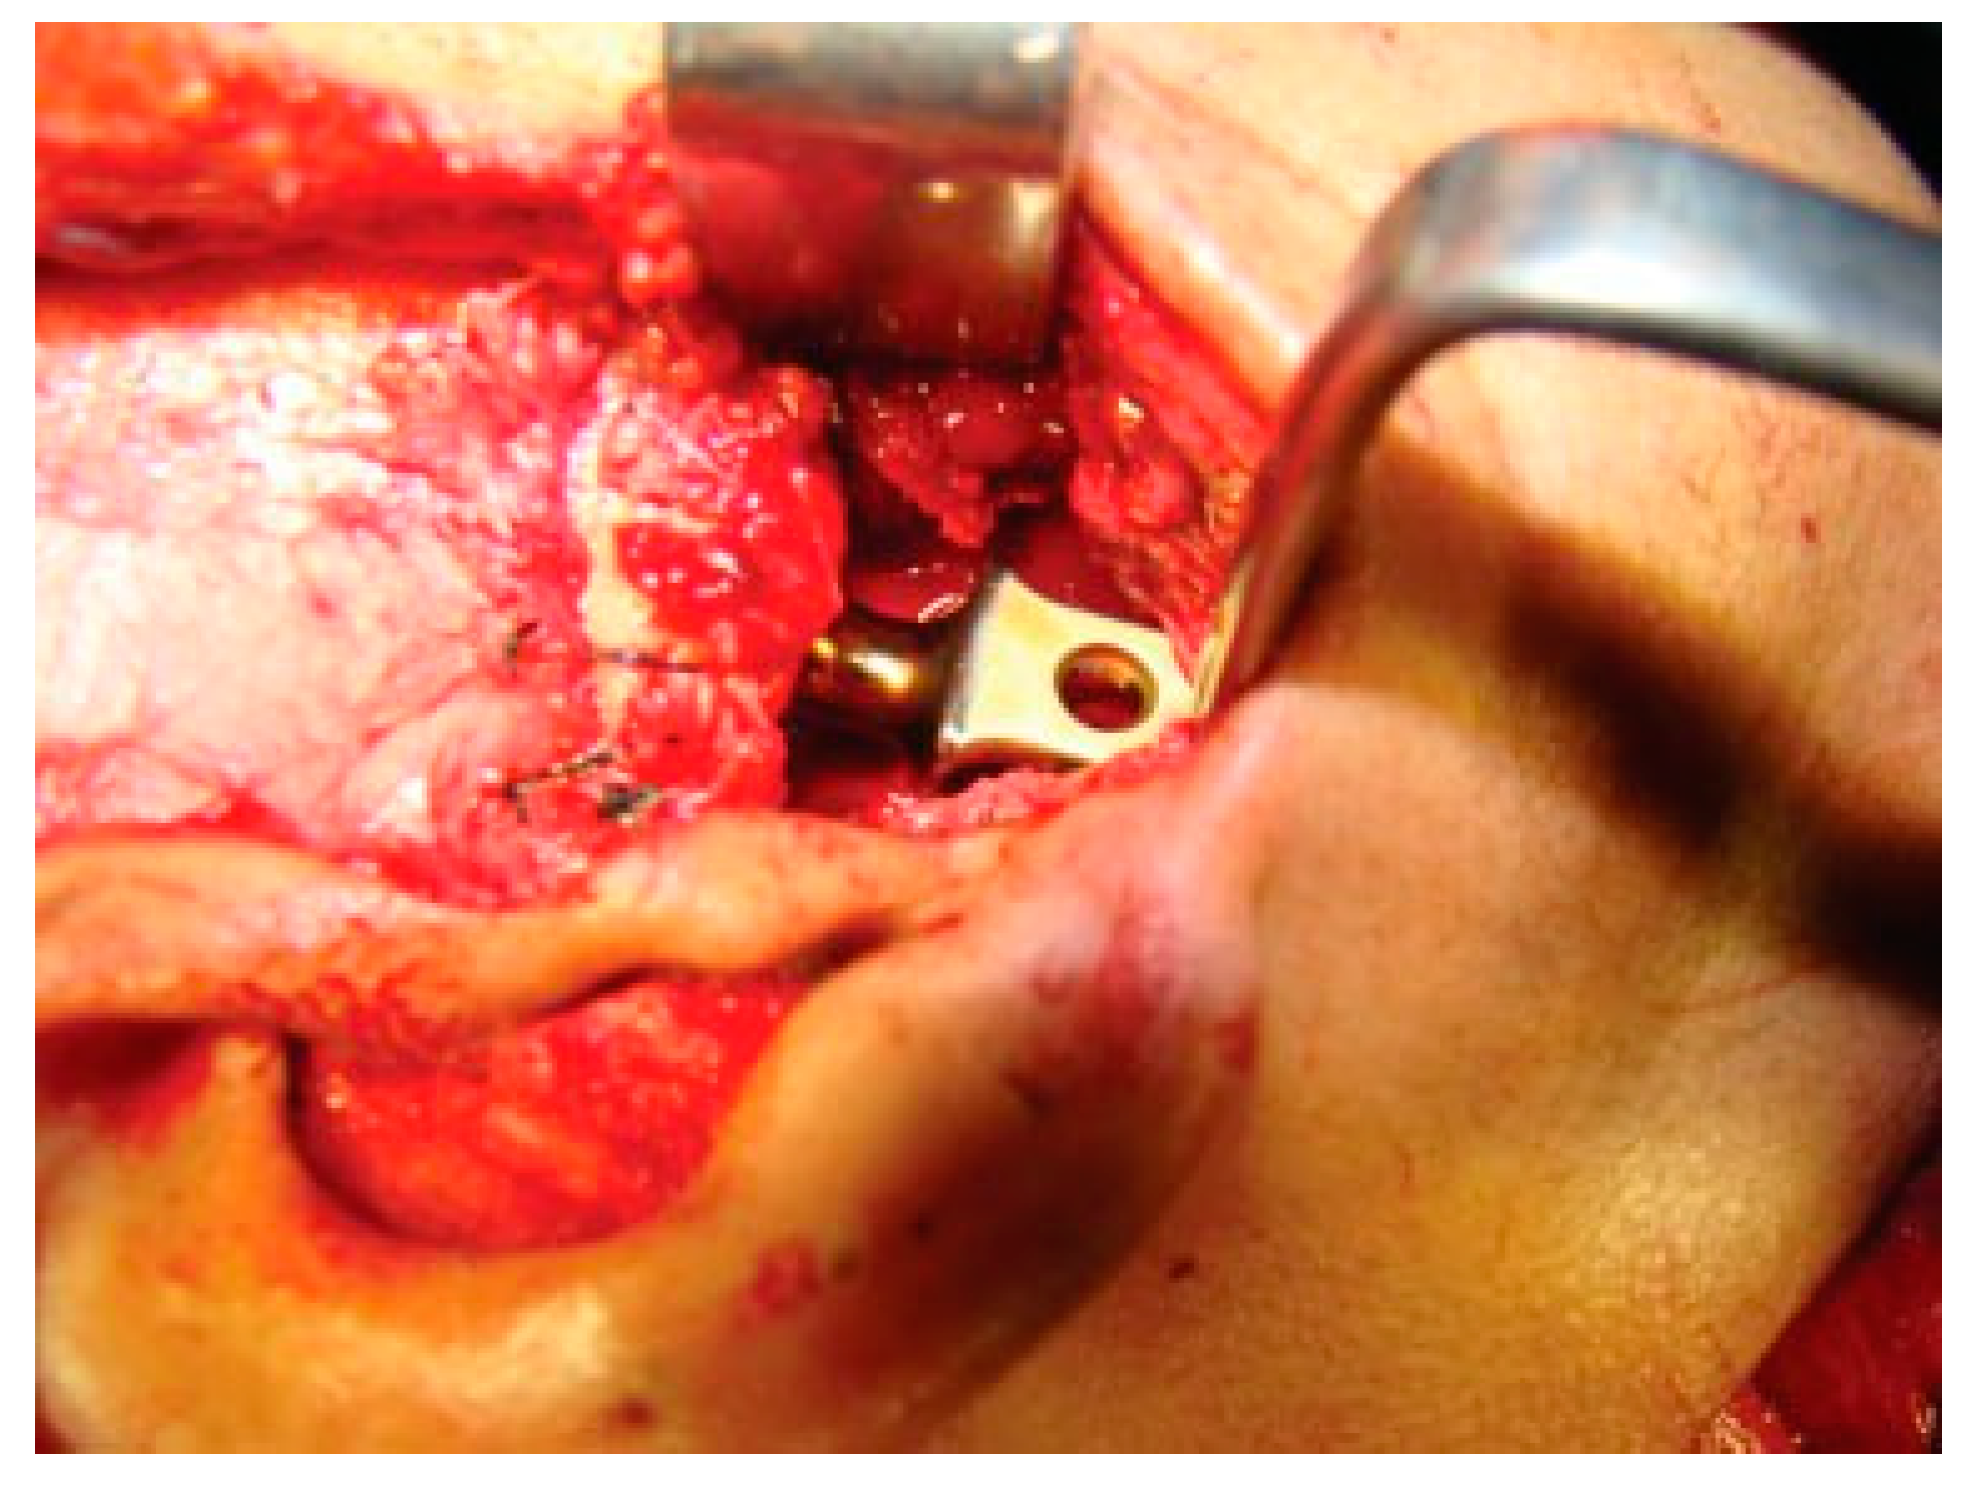

Figure 8. Temporalis muscle interpositioning.

Cmtr 09 i4f284 g008

Figure 9. Costochondral graft with temporalis muscle interpositioning.

Temporalis muscle was used in seven patients and temporalis fascia was used in two patients. In our series, using temporalis fascia as an interpositional material in the postoperative MIMO was 37 mm. Temporalis fascia has the disadvantage of being thinner, taut, and nonelastic. Long-term follow-up showed premature contact of teeth on the operated side in both the patients and the ramal height was not maintained. When the temporalis muscle was used as interpositional material, we based our flap on one of the branches of deep temporal arteries to maintain its vascularity and the flap was turned over the zygomatic arch and placed into the glenoid fossa. Temporalis muscle provided us with more bulk to obliterate the joint space and was sandwiched between the chondral end of the CCG and temporal bone. After appropriate positioning has been established, the muscle is sutured in both the anterior and posterior directions. Moreover, there is no hematoma formation and hence had better long-term stability. In patients where temporalis muscle was used, the MIMO was 41 mm and ramal height was maintained in all the cases (Figure 7 and Figure 8). The ramal height was preserved in most of our cases possibly due to unilateral ankylosis with compensation by the contralateral mandibular unit. Management of ankylosis in children can be very challenging and our aim was to correct retrognathia in bilateral cases and reduce the possibility of further asymmetry in unilateral cases. Growth center transplantation using CCGs was done in seven growing children in the 6- to 13-year age group. The uses of this biologically compatible autograft in reconstruction are benefits of growth potential and ability to remodel into a neocondyle with time. Unpredictable growth pattern of the CCG, midline shift, and donor site morbidity are some of the disadvantages of this technique. Overgrowth of the graft has been attributed to the use of a large cartilaginous cap; hence, only 1 to 2 mm cartilaginous cap must be used to avoid such complications [13,14,15]. We assessed the same using panoramic radiographs during follow-ups. The CCGs showed excellent mandibular growth along with complete integration of graft into the recipient site over the passage of time in all seven cases. The CCG was harvested from the sixth rib (contralateral side) using submammary incision and was secured using three 2-mm titanium screws at the recipient site. Due to the close proximity of the chondral cartilage to the base of skull, we routinely interposed temporalis muscle in these patients. The muscle pedicle acted as an artificial disc as well as a barrier between the base of skull and chondral cartilage (Figure 9). Early and vigorous mobilization is important to prevent postoperative adhesions and reankylosis [16]. The postoperative MIMO in seven patients was 41.5 mm. Asymmetry in the form of deviation of chin was found in one patient during long-term follow-up, where CCG overgrowth led to the deviation of the chin to the contralateral side.